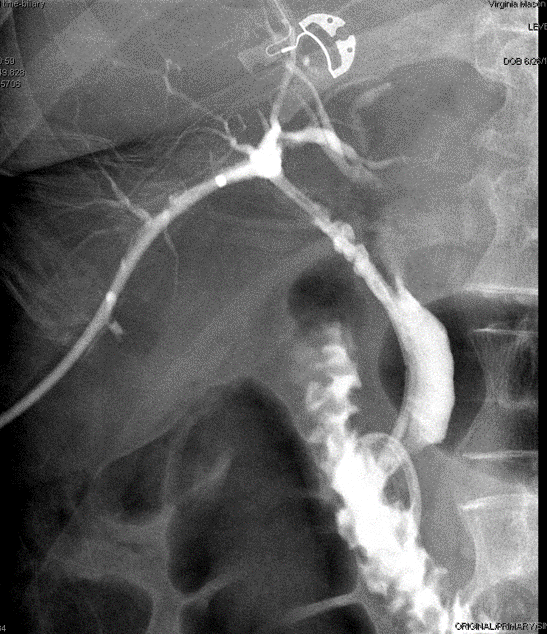

Following this, the patient experienced continued abdominal pain and bile in her JP drain 2 days post-operatively. An ERCP was performed (see cholangiogram in Figure 1) and a stent was placed into the CBD. It is evident from this cholangiogram that the right posterior sectional duct is not filling, consistent with either a Strasberg type B or C injury.

Figure 1. ERCP cholangiogram performed when bilious drainage was visualized post cholecystectomy from the JP drain in the gallbladder fossa.